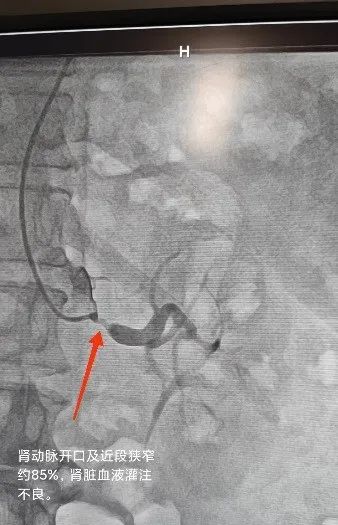

第一例患者既往高血压病史 20 余年,初期使用中效降压药即可控制,近年硝苯地平控释片 30 mg 每天两次、厄贝沙坦 150 mg 每天两次,血压仍然在 160/100 mmHg 左右。排查继发性因素时彩超发现患者左肾动脉重度狭窄及肾脏轻度萎缩,进一步肾动脉造影后明确左肾动脉开口及近段狭窄约 85%。经介入治疗后,肾动脉狭窄解除,血流恢复。